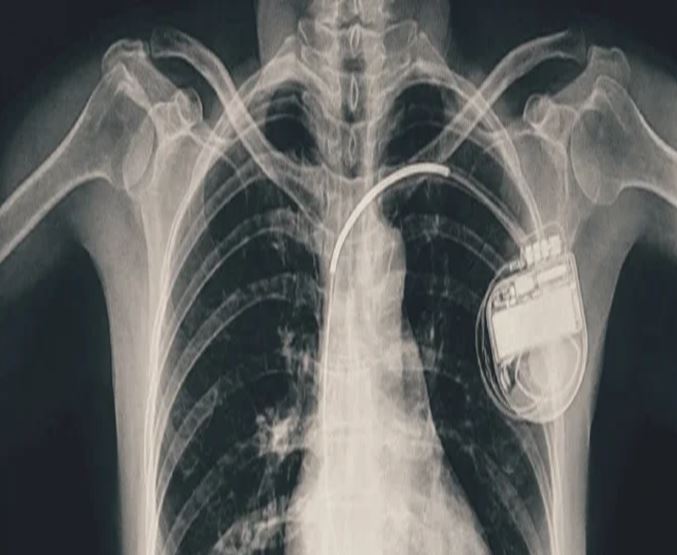

भोपाल। भोपाल मेमोरियल अस्पताल एवं अनुसंधान केंद्र (बीएमएचआरसी) के कार्डियोलॉजी विभाग ने एक दुर्लभ और चुनौतीपूर्ण चिकित्सा उपलब्धि हासिल की है। यहां 13 वर्ष की गैस पीड़ित आश्रित बालिका को इमरजेंसी में डुअल चेंबर पेसमेकर लगाकर उसकी जान बचाई गई। अब बालिका की हालत बेहतर है और उसे अस्पताल से छुट्टी दे दी गई है। यह प्रक्रिया सहायक प्रोफेसर डॉ. अमन चतुर्वेदी और उनकी टीम द्वारा सफलतापूर्वक की गई।

तीन वर्ष की आयु में दिल में था छेद

बीएमएचआरसी के कार्डियोलॉजी विभाग के सहायक प्रोफेसर डॉ. अमन चतुर्वेदी ने बताया कि यह मरीज जन्म से ही हृदय रोग से पीड़ित थी। तीन वर्ष की आयु में उसके दिल में छेद (congenital heart defect) का ऑपरेशन किया गया था। ऑपरेशन के बाद उसे हार्ट ब्लॉक हो गया यानी हृदय की धड़कन असामान्य रूप से धीमी हो गई। इसके कारण उसे चक्कर आना, आंखों के सामने अंधेरा छा जाना जैसी परेशानियां होने लगीं।हार्ट ब्लॉक की स्थिति में, बचपन में ही उसे एपिकार्डियल पेसिंग (epicardial pacing) डिवाइस लगाई गई। इस प्रक्रिया में पेसमेकर के तार हृदय की बाहरी सतह पर लगाए जाते हैं, जो आमतौर पर छोटे बच्चों में अपनाई जाती है, क्योंकि उनके हृदय का आकार छोटा होता है। इस डिवाइस की आयु लगभग 10 वर्ष होती है। डिवाइस की अवधि पूरी होने के बाद हाल ही में मरीज को फिर से वही लक्षण होने लगे। बीएमएचआरसी में जांच के बाद यह स्पष्ट हुआ कि अब उसे एक स्थायी और अधिक उन्नत पेसमेकर की आवश्यकता है। आपातकालीन स्थिति में टीम ने सफलतापूर्वक डुअल चेंबर पेसमेकर प्रत्यारोपित किया। इस जीवनरक्षक प्रक्रिया को अंजाम देने वाली टीम में कार्डियोलॉजी विभाग के सहायक प्रोफेसर डॉ. कपिलकांत त्रिपाठी, डॉ. नुपुर गोयल, मेडिकल ऑफिसर डॉ. अनुराग ठाकुर एवं अन्य सदस्य शामिल थे।

पेसमेकर एक छोटा उपकरण होता है, जो दिल की धड़कन को नियंत्रित करता है। यह दिल को सही गति से धड़कने में मदद करता है। सिंगल चेंबर पेसमेकर हार्ट के सिर्फ एक चेंबर को इलैक्ट्रिक सिग्नल देता है, जबकि डुअल चेंबर पेसमेकर दिल के दो भागों-ऊपरी (एट्रियम) और निचले (वेन्ट्रिकल) चेंबरों को दोनों को सिग्नल भेजता है, जिससे दिल की धड़कन और भी प्राकृतिक तरीके से चलती है। बच्ची के मामले में डुअल चेंबर पेसमेकर इसलिए लगाया गया क्योंकि उसकी स्थिति अधिक जटिल थी और बेहतर तालमेल के लिए दोनों चेंबर तक एकसाथ सिग्नल देना ज़रूरी था।